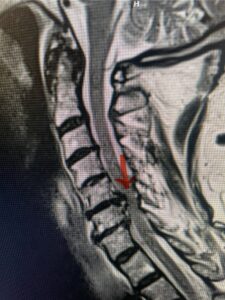

Another patient, a 77 year-old female, presents with pain, numbness, and weakness of her arms and difficulty with balance over a 6-month period. MRI revealed severe osteophytic disease at C5-C7 with cord compression (Fig. 4). Further work-up by fine-cut cervical CT to evaluate the nature of compression revealed a completely calcified osteophyte (Fig. 5). Although the patient had a good lordosis and a posterior cervical approach would accomplish an adequate decompression, we elected to perform a two-level anterior cervical discectomy and fusion. This particular osteophyte is formidable because of its size but the compression was all anterior and would be a less invasive approach. Fortunately, during the procedure, the patient had a fair amount of osteoporosis which allowed the osteophyte to be drilled and bit away with considerable ease. Interestingly, the C6 7 osteophyte which was more a sheet of osteophyte was more challenging to remove. In the end the decompression went well, and we placed two interbody devices filled with bone graft with plates at each level (Fig. 6). The patient had a nice recovery with immediate reduction of pain and numbness. This case demonstrates the importance of recognition of cervical myelopathy in its early stages. A significant reversal of function is generally the rule if the patient has appropriate correlative findings on exam and MRI, particularly with long tract distribution weakness development within a year time period.

Figs 4a: Sagittal and axial T2-weighted cervical MRIs demonstrating large osteophyte worse at C5-6 compressing spinal cord more eccentrically to the left (red arrows)